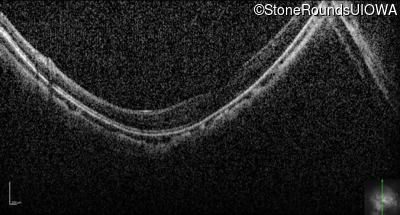

OCT Stack